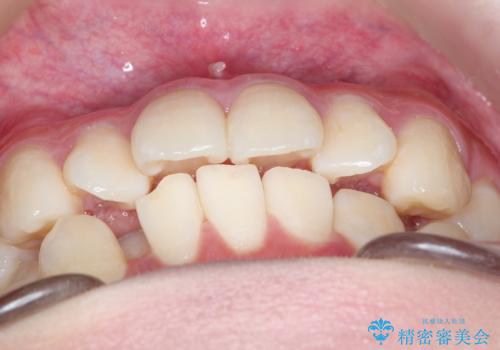

- 上下の前歯に捻れ(捻転)とガタつき(叢生)が見られます。

上の2番目の前歯の捻れに関しては、元々歯の大きさが小さい歯であるため、マウスピースにて力がかかりにくく、捻転の改善が一般的に難しくなりがちです。

下の犬歯に関しても捻れと傾き、ガタつきが大きく、歯根の長さも相まって移動の難易度が高くなりがちです。